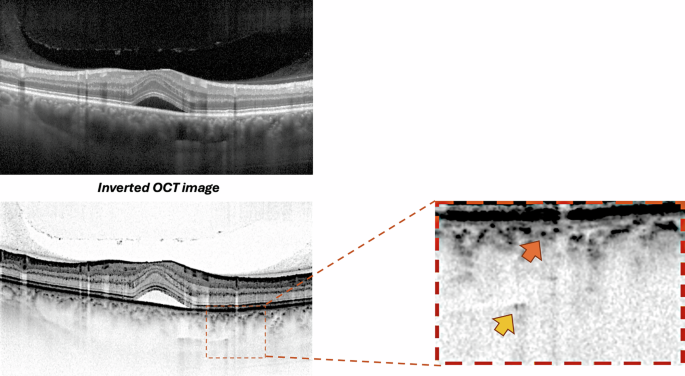

Prior to quantifying HCF, two experienced graders (PV and EB) reached consensus on identifying and delineating each choroidal layer in the OCT sections following established methodology [9]. Haller’s layer was defined as the outermost choroidal layer housing the large choroidal vessels, while Sattler’s layer was described as the region containing medium-sized choroidal vessels, appearing as medium-sized, less intense spaces surrounded by more intense stroma (Fig. 1). The choriocapillaris was characterized as the less reflective layer situated above Sattler’s layer and encompassing Bruch’s membrane as well [6, 21].

Representative OCT B-scan demonstrating the standardized protocol for hyperreflective choroidal foci identification and quantification. Top panel: Standard OCT B-scan of a patient with CSC showing subretinal fluid and choroidal thickening. Middle panel: Inverted OCT image, enhancing visualization of choroidal hyperreflective foci through improved contrast. Right panel: High-magnification view of the choroidal area showing hyperreflective foci in Sattler’s layer (orange arrow) and Haller’s layer (yellow arrow).

HCFs were defined as round or oval areas with high reflectivity, appearing black or white in color on white-over-black and black-over-white images, respectively, with a diameter between 10 and 50 micrometers [9, 10, 20]. Two independent observers (PV and EB) counted the number of HCF in different layers of the choroid, including the choriocapillaris-Sattler’s layer complex, and Haller’s layer (Fig. 1). The identification and counting were performed on high-magnification white-over-black spectral-domain OCT images to improve the identification of hyperreflective foci in the choroid [9, 10]. For hyperreflective foci quantification, both readers counted foci in each designated choroidal layer following the standardized protocol [9, 10]. The values provided by both graders were utilized to evaluate intergrader repeatability. The average of the ratings from the two graders was incorporated into the final analysis. One of the graders (PV) conducted the grading process twice on different days to determine intragrader repeatability. In cases where foci counts differed by more than 20%, a third experienced reader (FB) performed the quantification, and the median value was used for analysis. The intraclass correlation coefficient was calculated to assess inter-observer agreement for foci quantification.